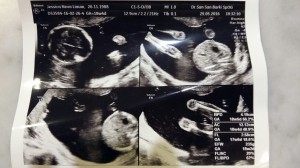

Today we went for our appointment, meeting our baby no. 2 who’s growing healthy and well. At this stage, baby no. 2 is slightly lighter than N. Our obgyn said that he’s 70% sure of the gender. I actually think that he’s 100% sure but to avoid disappointment, he told us to wait for another month. Oh well…